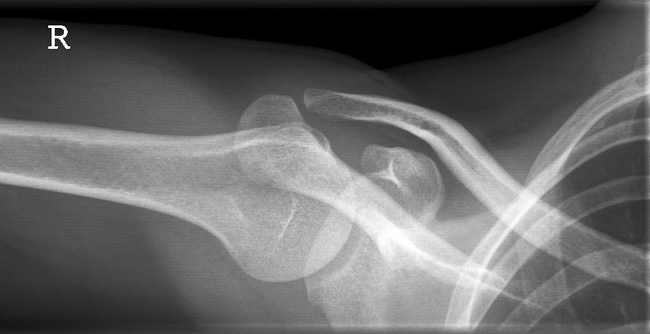

Schulter nach Morrison oder Outlet View

Indikation

v.a. Impingementsyndrom: Beurteilung des Akromions, des AC-Gelenks, evtl. hilfreich zur Diagnostik von Luxationen

Beurteilungskriterien

- Impingementsyndrom (2): Neigungswinkel des Akromions -> Je gebogener bzw. hakenförmiger desto höher ist die Wahrscheinlichkeit. Radiologische Befunde: Zystenbildung im Bereich des Tuberculum majus? Subchondrale Sklerosierung am Tuberculum majus oder subacromiale Osteophytenbildung? Verkalkungen im Verlauf der Supraspinatussehne?

- subacrominalen Raumes: normalerweise 1 - 1,5 cm, < 10 mm -> wahrscheinlich, < 6 mm -> sicher pathologisch